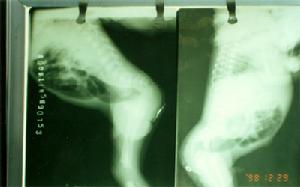

先天性肛門閉鎖對本病的診斷,主要根據患兒哭時隨著腹壓的增高或降低,會陰部也隨著凸起或凹陷。用一手輕壓迫下腹部,一手觸摸會陰部,則有波動感。若將患兒臀部抬高,肛門部扣診呈鼓音。X線可幫助進一步確診。

③肛門直腸閉鎖:肛門處可見凹陷,但與直腸尾端之間相隔的距離大,直腸尾端在肛門直腸肌環以上,又叫高位鎖肛,該種鎖肛症較多見。

先天性肛門閉鎖據介紹,接診的3名先天性肛門閉鎖患兒,是分別從南京市兒童社會福利院、鎮江市兒童社會福利院送來的,患兒出生後發現無肛門,幾天后就被父母遺棄,由於無法正常排便,造成腹脹、腹腔內感染、腸道梗阻,可憐的小生命被人發現送到醫院時,肚子脹得像大鼓。男孩明明是出生後第四天被遺棄的,兒童福利院緊急將他送到中大醫院,來院時患兒臉色發青,不斷嘔吐,情況危急,但是由於檢查發現為高位肛門閉鎖,直腸與肛門之間距離較遠,普外科專家緊急為患兒在腹部造瘺,臨時解決“出口”問題,等孩子康復後再擇期進行肛門成形手術。